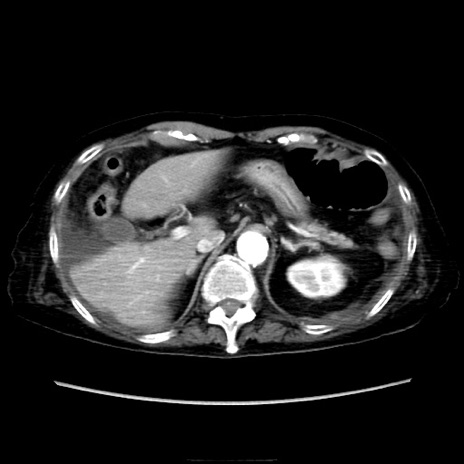

他院CT

横断像